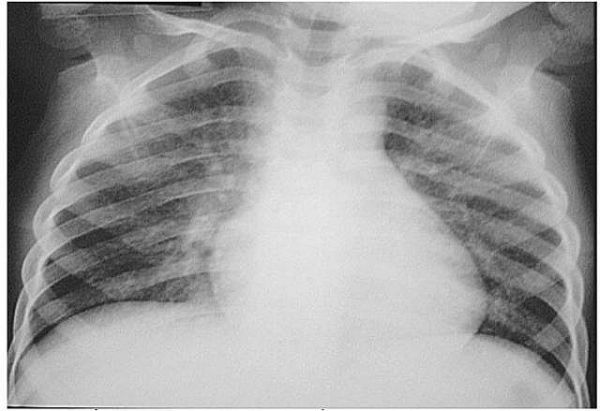

Viêm phổi do sặc dầu